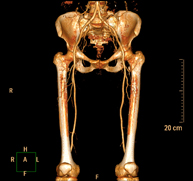

- Aortoiliac CT angiography

A non-invasive diagnostic test that involves examining the iliac arteries and abdominal aorta, obtaining high-definition anatomical images using CT (computed tomography) equipment and iodinated contrast dye. With the aid of workstations specialised for arterial studies, the image quality supports 2D and 3D reconstructions. This test is particularly recommended as a pre-surgical study (vascular map) prior to percutaneous or surgical interventions on the abdominal aorta, as a complementary study in patients with lower limb ischaemia, etc.

Consiste en obtener una muestra de tejido de una determinada lesión ósea. En ocasiones se realiza bajo sedación, con la ayuda del equipo de anestesia. Se utilizan agujas que permiten la obtención de un cilindro de la lesión a estudiar, que se enviará a Anatomía Patológica para su análisis histológico. Todo el procedimiento se realiza controlado con imágenes obtenidas por Tomografía Computarizada (TC) en varios momentos de la biopsia, mediante el empleo de Fluoroscopia-TC. Tras la prueba, el paciente permanece hospitalizado para controlar su evolución. Es necesario aportar pruebas de coagulación antes de la punción. - Angio-TC arterial extremidades inferiores

Prueba diagnóstica no invasiva que consiste en el estudio vascular del sector aorto-ilíaco y de los vasos arteriales de ambas extremidades inferiores obteniendo imágenes de alta definición anatómica mediante el empleo de un equipo de TC Multidetector de última generación y de contraste yodado. La calidad de las imágenes permite realizar reconstrucciones en 2D y 3D gracias a estaciones de trabajo especializadas en el estudio arterial.